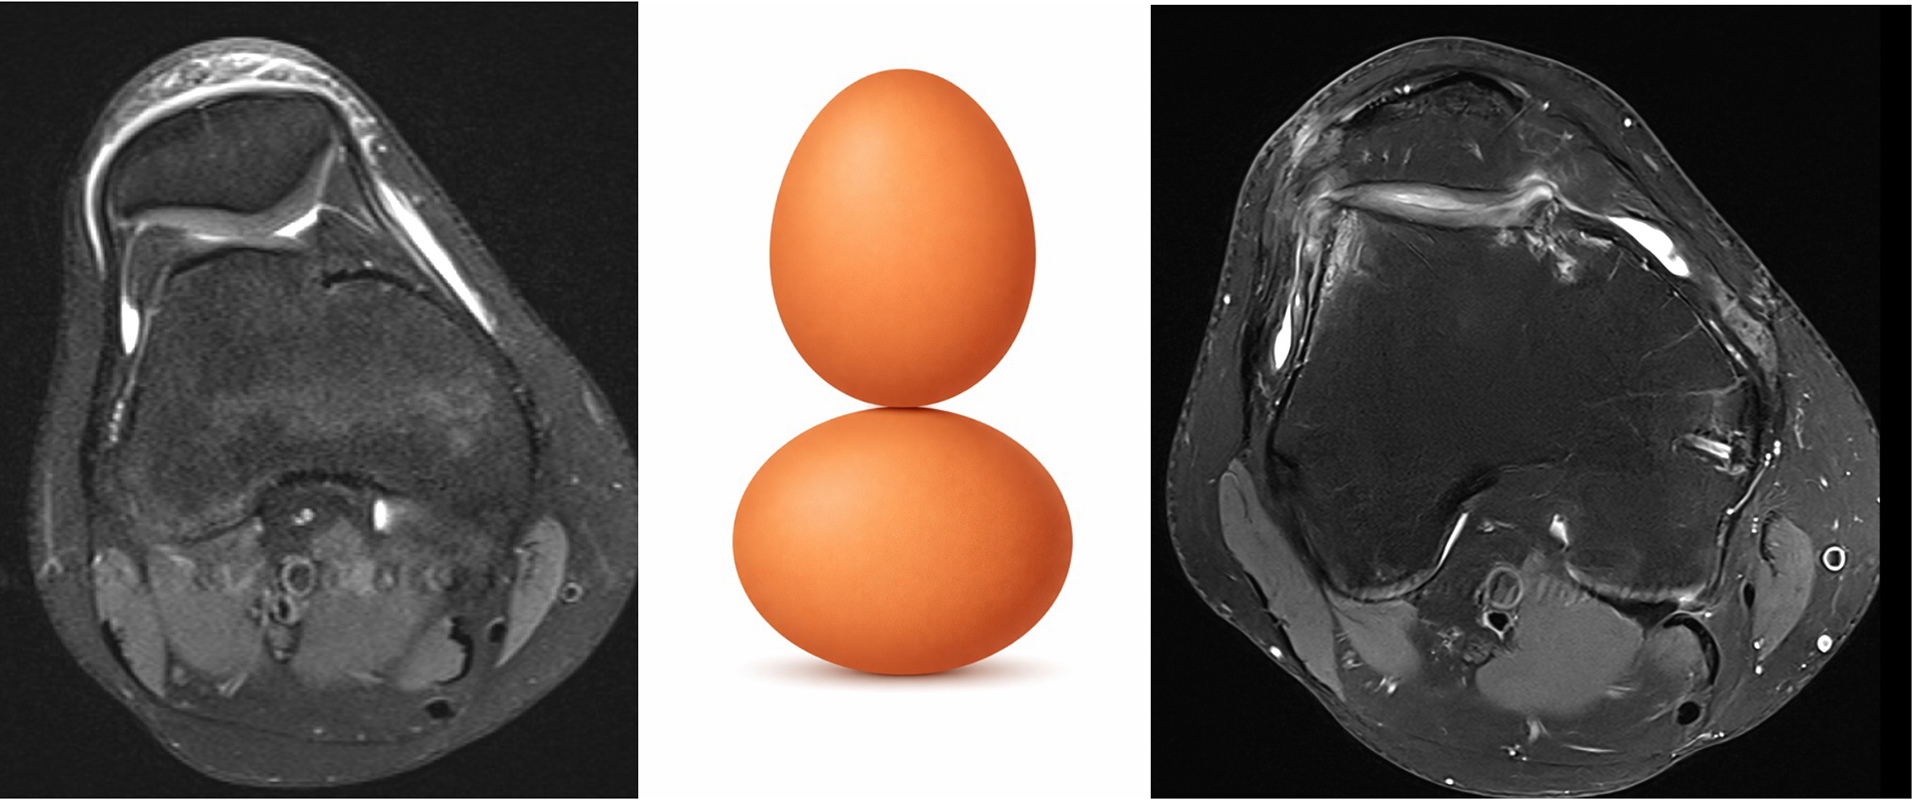

1. Trochleadysplasie (Form des Gleitlagers)

Ein flaches oder fehlgeformtes Gleitlager bietet der Patella besonders in Strecknähe wenig knöchernen Halt. Hochgradige Dysplasien sind einer der stärksten Prädiktoren für Rezidive. Therapeutisch ist relevant: In ausgewählten Fällen kann eine Trochleoplastik (Formkorrektur) sinnvoll sein – sie ist jedoch ein spezialisiertes Verfahren mit klaren Indikationen.

2. Hochstehende Patella

Steht die Patella „zu hoch“, gleitet sie erst spät in die Trochlea ein. Dadurch fehlt in den ersten Beugegraden die knöcherne Führung – genau dort passieren viele Luxationen. Bei deutlichem Patellahochstand kann ein nach unten Versetzen des Kniescheibensehnenansatzes die Kniescheibe stabilisieren.

Bildgebung ist mehr als nur ein MRT

Für die Therapieplanung braucht es eine saubere Risikoanalyse: klinische Tests plus Bildgebung. Röntgen, MRT und ggf. CT helfen, die „Treiber“ zu identifizieren – genau das ist die Grundlage des individualisierten Therapieansatzes.